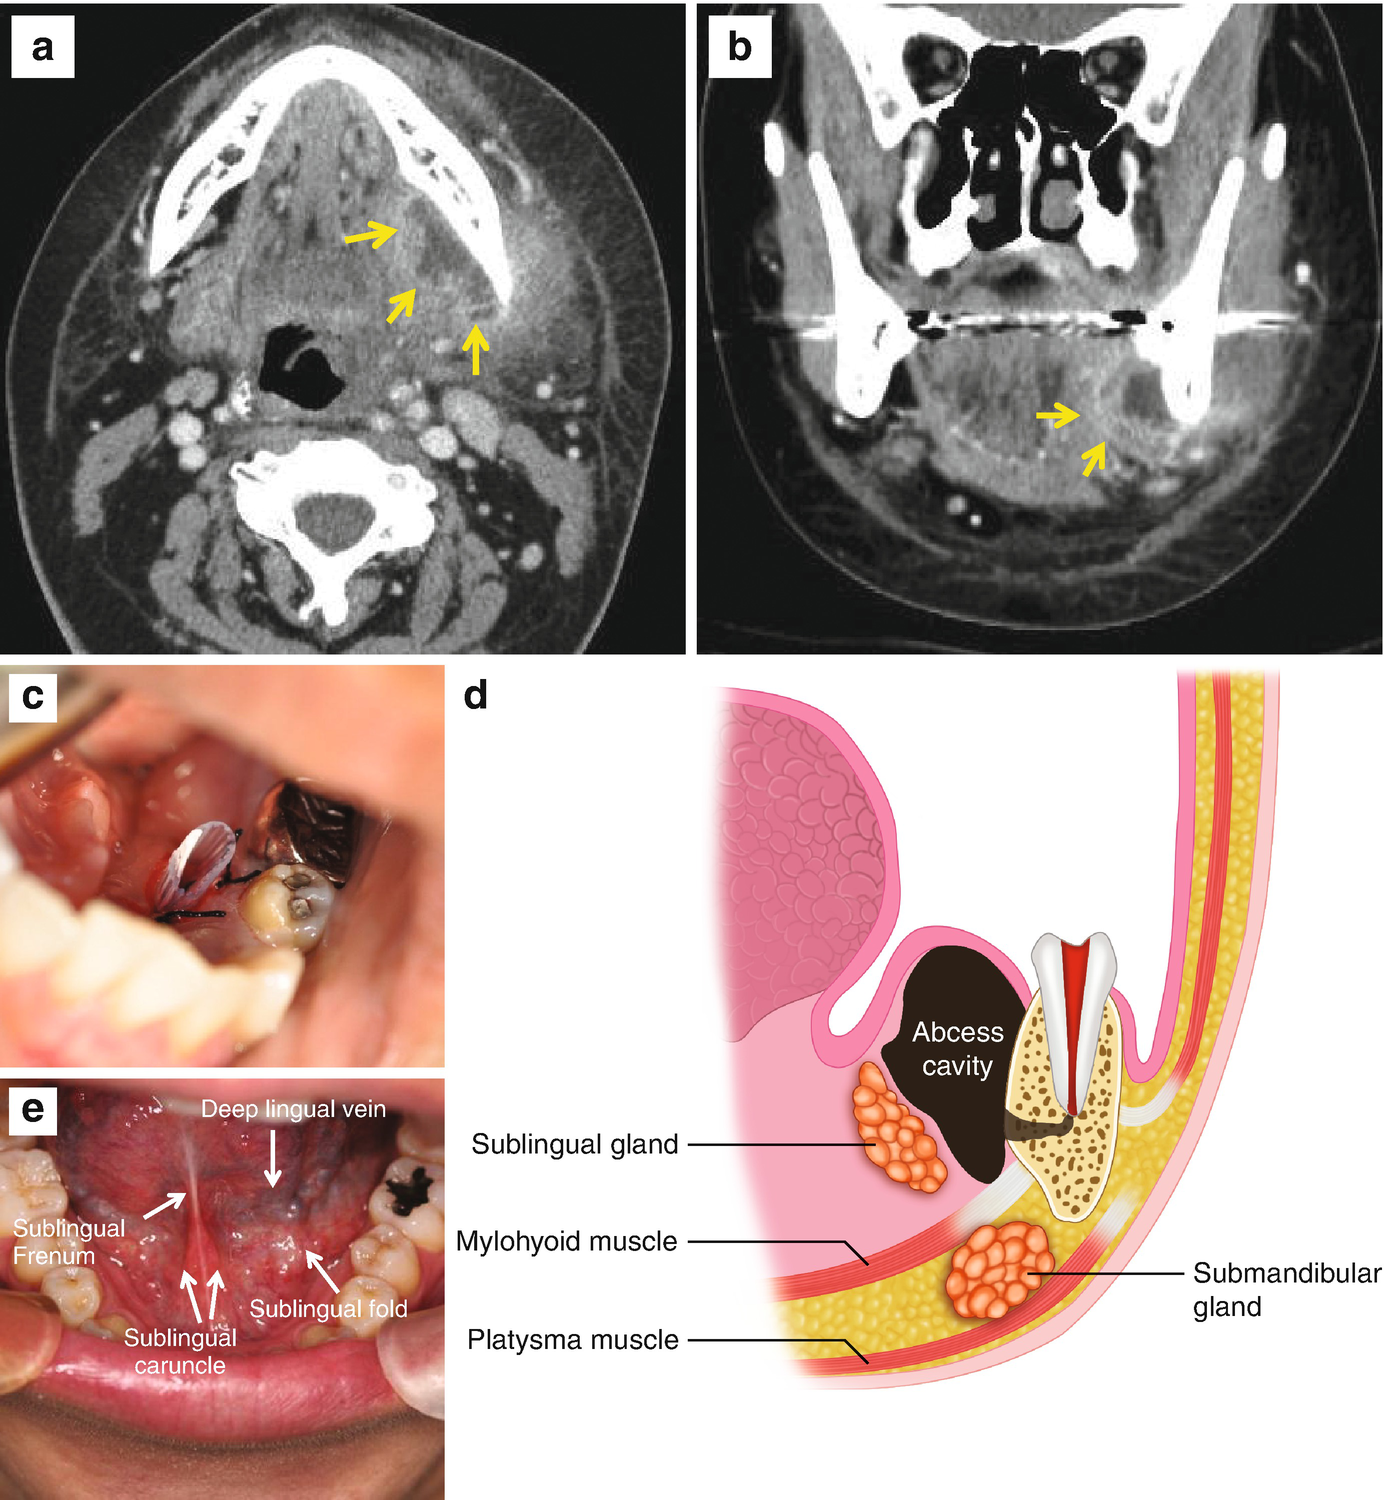

submandibular and sublingual spaces

submandibular space diagram